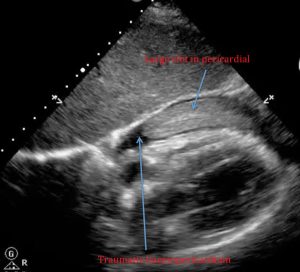

4.4 Ventana pericárdica

Modo: Sectorial

Profundidad: 18–22 cm

Buscar:

-

Derrame anecoico pericárdico

Signos indirectos de compromiso hemodinámico (según entrenamiento)

Derrame pericárdico traumático